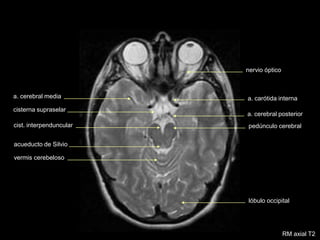

RM axial T2

cristalino

celdillas etmoidales

tallo hipofisario

nervio óptico

cist.supraselar

cist. interpenduncular

acueducto de Silvio

vermis cerebeloso

lóbulo occipital

a. cerebral media